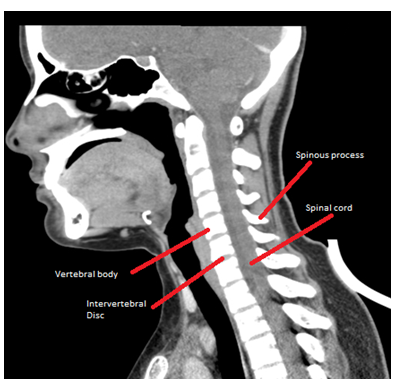

Between the vertebral bodies is the intervertebral disc (Figure 1 & 2), a cartilaginous structure that fulfills the double function of giving primary support to the spine and sufficient elasticity to allow movements of the spine,1 which normally has a biconvex shape.4 This disc is composed of central part by a nucleus pulposus (containing up to 88% of water in young and healthy discs1) that is externally contained by a fibrous annulus.3

Figure 1 Sagital view-Cervical computed tomography.